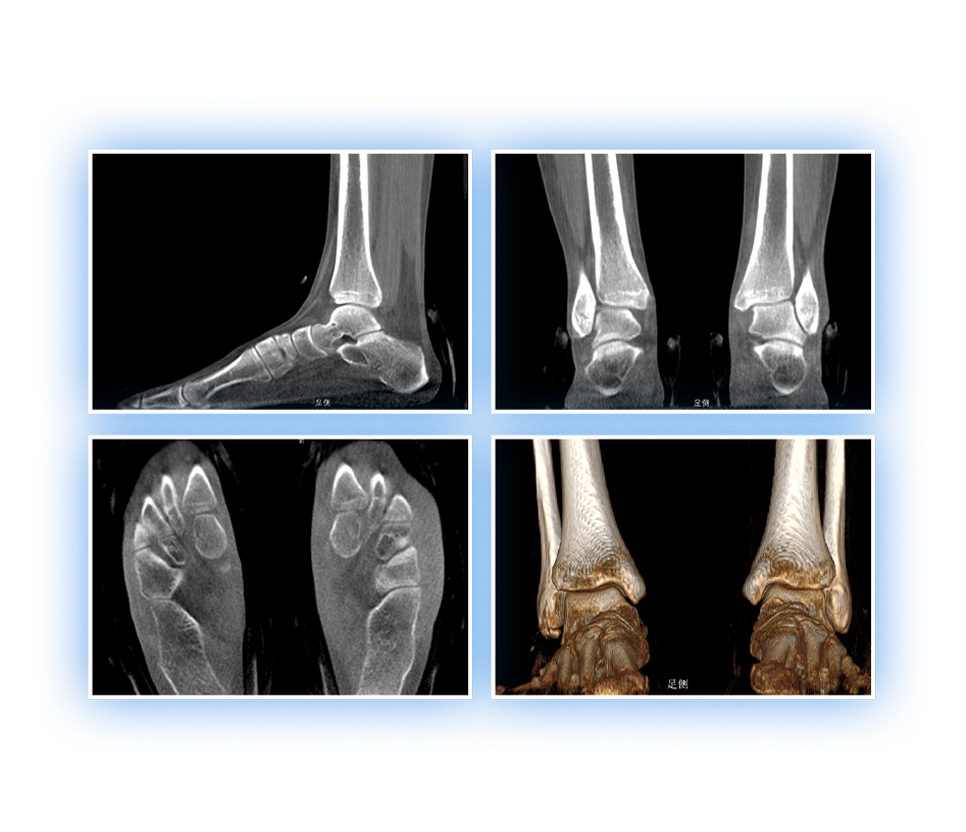

• 足踝

2D+3D一站式快速检查

支持双腿或双侧髋关节扫描 | 方便对比,降低漏诊误诊

FOV 350mm